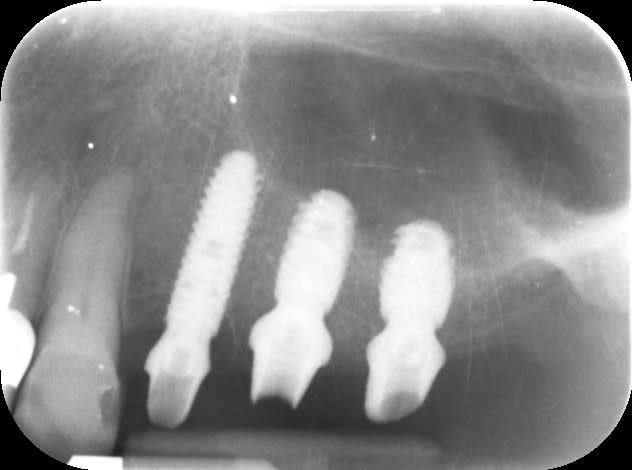

Pose de la prothèse aujourd'hui. serrage à 25N, scellement avec temp bond LT, sous occlusion légère. Contrôle dans 6 mois.

Ça finit plutôt bien.

L'expansion de la crête, je n'en ai jamais vu, jamais fait. J'ai fait un lambeau et suivi l'axe de la crête 3,4 a passé en sous forage. Mais impossible de faire du transvissé car l'axe est vestibulaire (sauf avec les MU que j'évite d'utiliser).